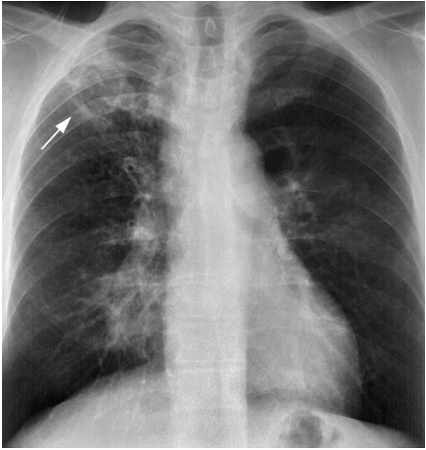

Q

Diagnose?

A

Hjertesvigt